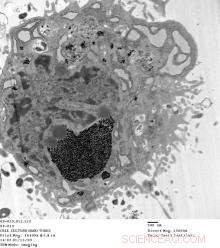

Dark spots are aggregates of gadonanotubes (GNTs) in the cytoplasm of a mesenchymal stem cell. Tests show GNTs are highly effective for tagging and tracking stem cells through magnetic resonance imaging. (Credit: Lesa Tran/Rice University)

Researchers at Rice and the Texas Heart Institute at St. Luke's Episcopal Hospital in Houston reported in the journal Biomaterials that mesenchymal stem cells drawn from pig bone marrow labeled with GNTs are easily spotted under MRI. The technique holds promise for tracking the progress of tagged cells as they travel through a patient's body.